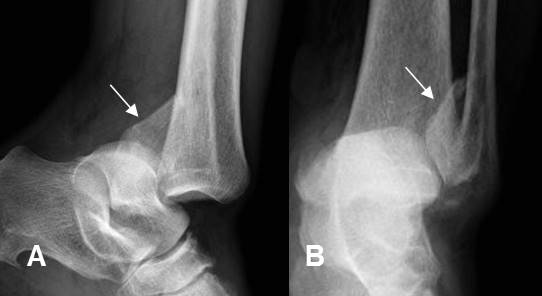

Fig 159. Subluxación.

A: Rx AP. No se identifican alteraciones.

B: Rx lateral. Aumento del espacio entre el epicóndilo medial y la cavidad coronoides, por subluxación.